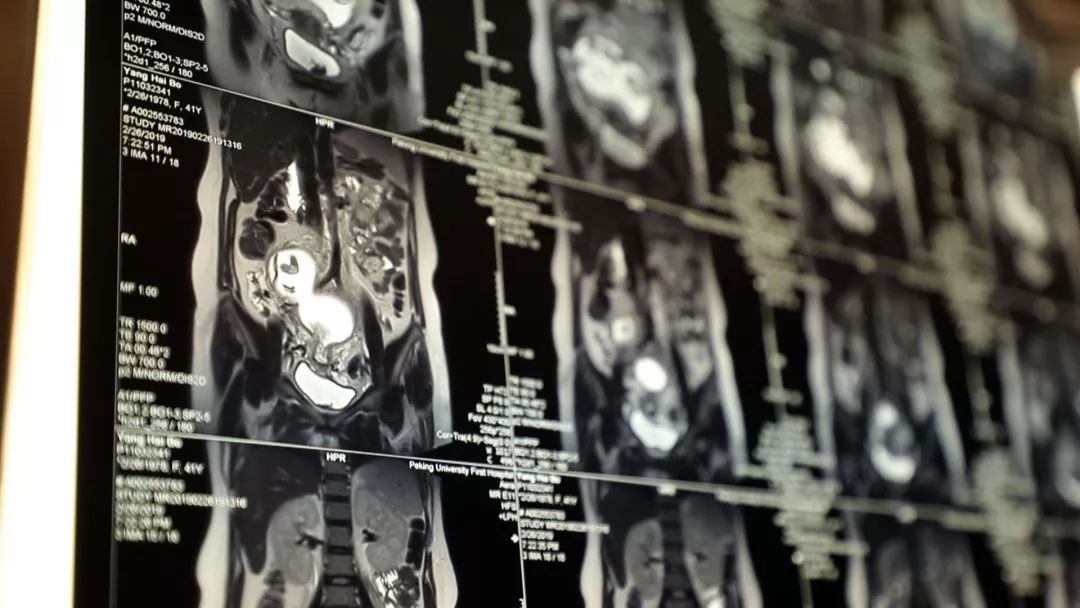

41岁的杨海波再次怀孕了,可她7岁的大女儿糖宝,似乎并不能接受。在杨海波心里,一直认为糖宝是因为不想被分享宠爱,才抗拒她肚子里的小宝宝,但事实上,糖宝有另外的担心,她在大人的只言片语中发现,怀了孕的妈妈,可能会有生命危险。原来,杨海波在产检中发现,右肾有一片阴影,经过核磁检查确认,是肾癌。

肿瘤的治疗,一定是越早越好。北京大学第一医院泌尿外科的张争大夫,从医近二十年,对于像杨海波这样的肿瘤患者,他有一套很成熟的治疗方式,预后效果也会很好。但棘手的是,这个成熟的治疗方式,会对杨海波肚子里面的胎儿产生不好的影响,甚至有流产的可能。在妇产科主任的杨慧霞大夫的眼里,杨海波作为一个高龄、有剖腹产史的高危孕妇,情况同样不容乐观。

此时进行手术,对胎儿来说,风险巨大。但如果等胎儿出生之后再手术,肿瘤是否会发生扩散、发生转移、发生破裂,甚至威胁生命,谁都无法确定。一面是可能威胁生命的疾病,一面是心爱的孩子,杨海波将做出怎样的选择呢?